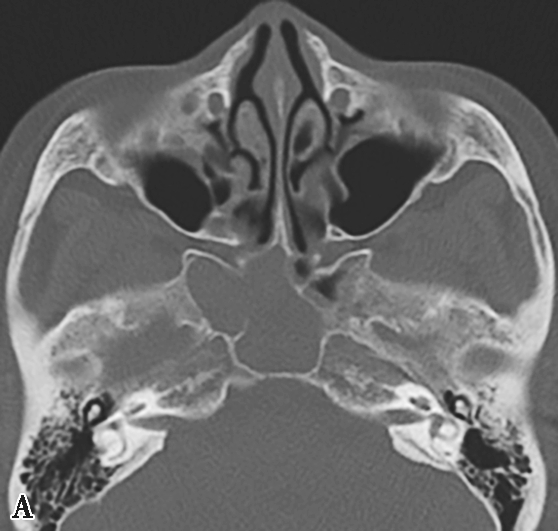

图1-3-22 变应性真菌性鼻窦炎

A、B.横断面、冠状面CT骨窗,示双侧上颌窦、筛窦腔膨胀,窦腔充填软组织密度影,病变内部可见片状磨玻璃样密度增高影,上颌窦壁骨质增生硬化;C.横断面CT软组织窗,示病变内部磨玻璃样密度影显示更清楚